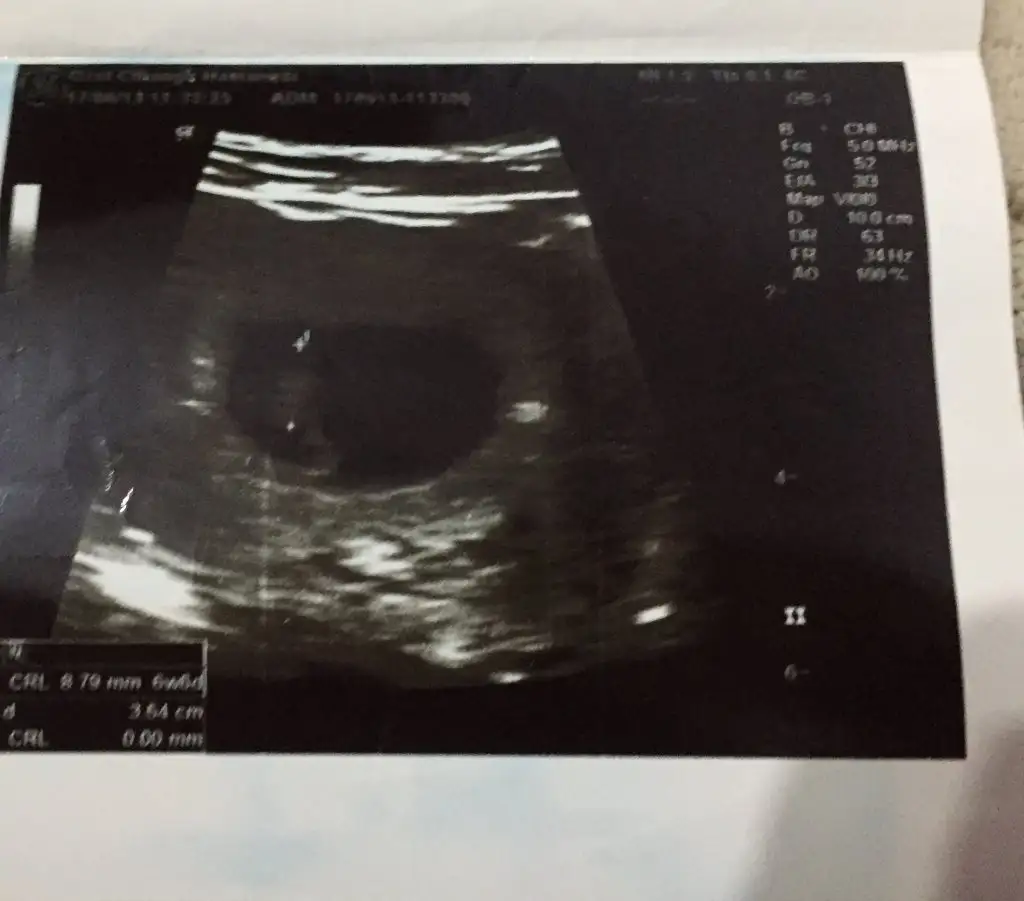

Canım bende şimdi oğlumun eski ultrason görüntülerine baktım, ilk ultrasonda solda görünüyor, oğlumda tutmuş bu teori

• 4D72C95C-19F2-4AD8-9E24-8963E9191763.webp

22,8 KB · Görüntüleme: 62

Oğluma bakayım bende ama sanki oda soldaydi.Bu minnak bayağı sağ tarafta Allah'ım konuyu biliyorsun hayırlısı ile amin